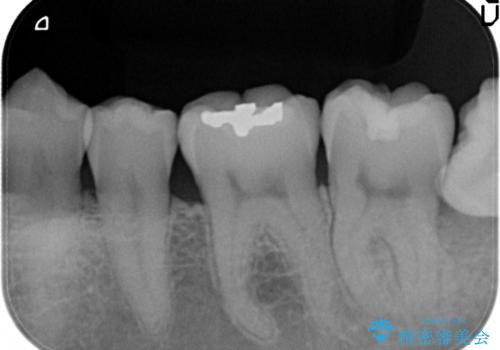

メタルフリー セラミックインレー

- メタルフリーの治療を希望されて来院されました。

セラミックインレーの治療を2回の来院で終了しております

e-max プレスインレーにて修復治療を行っているため適合性及び審美性の高い治療を行うことができます